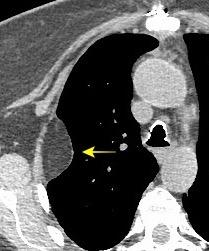

Signos en decúbito supino

175 cc

Dec. supino

Líquido en cisura horizontal y accesoria derecha